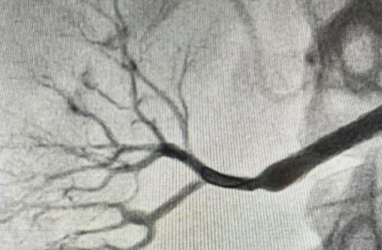

Пациентка поступила в Региональный сосудистый центр с резкими скачками артериального давления. Исследование компьютерной томографии показало критический стеноз правой почечной артерии, практически полностью заблокированной фиброзной тканью.

Впервые столкнулись с болезнью Ормонда в своей практике, — подчеркивает рентгенэндоваскулярный хирург Вячеслав Воробьёв. — По результатам детальной диагностики, подтвердившей функциональность почки, было решено срочно проводить оперативное лечение, иначе пациентка рисковала потерять орган.

Для уникальной процедуры медики использовали специальный индивидуально изготовленный стент, выдерживающий высокие нагрузки. Сложнейшая операция продолжительностью около 30 минут прошла успешно под руководством завотделением рентгенохирургических методик Никиты Грачева.